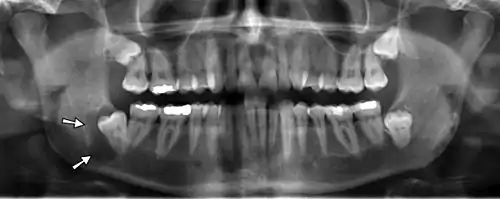

Dental panoramic radiograph showing dentigerous cyst (arrowed).